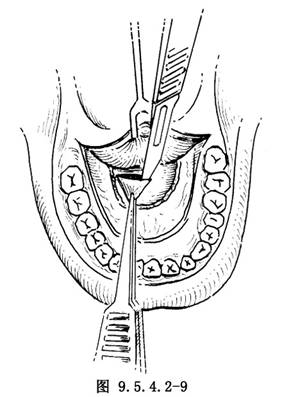

(4)切開鼻腔側黏骨膜,探查腫瘤基底部及擴展方向:小心切開鼻腔側黏骨膜後,即可看見腫瘤。以示指伸入鼻咽腔,探查腫瘤基底附着部位,擴展方向,顱底骨質有無破壞、缺損,再確定是否需要再擴大術野或經鼻頜途徑的配合。操作必須小心輕柔,儘量避免損傷腫瘤表面,以免在切除之前即已出現難以控制的出血,增加手術困難(圖9.5.4.2-9)。